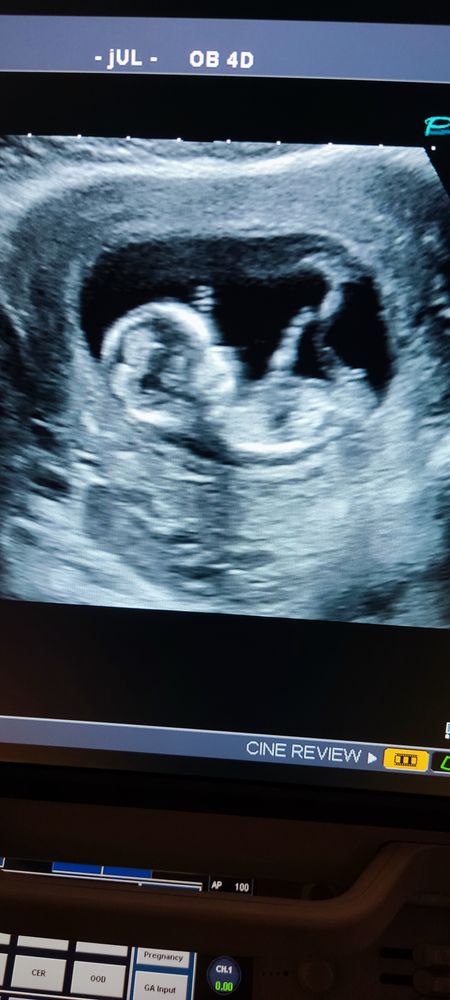

Тамара в Здоровье будущей мамы 3 года Первый скрининг Результаты: УЗИ, КТГ, доплера, скрининга Девочки, сегодня был первый скрининг, на УЗИ пол не сказали, а вы как думаете? Посмотрите еще 20 записей на эту тему Отменить Ответить Анна Мальчик 💙пацан! 14.07.2022 Ответить Anna Fort Мне кажется, что мальчик. Уж больно высоко половой бугорок расположен. 14.07.2022 Ответить Тамара Anna Fort, только сказали что это пуповина, ну мне другое видется 14.07.2022 Ответить Oksana Думаю, у вас будет ребёнок 😂 14.07.2022 Ответить Тамара Oksana, это точно) 14.07.2022 Ответить Юлия Sonnце Вроде как, девочка, если я правильно рассмотрела половой бугорок. 14.07.2022 Ответить Тамара Юлия Sonnце, спасибо, мне почему-то тоже так кажется) Жаль со старшим нет такого фото 14.07.2022 Ответить Marina Такой клевый малыш))) (тттт) на вас. Нам на 1 скрининге наврали жестко, поэтому я даже не загоняю на этот счет)) 14.07.2022 Ответить Тамара Marina, спасибо 14.07.2022 Ответить Первый скрининг Когда у вас перевернулся малыш? Чаты Беременных Выберите чат: Январята-2026 Февралята-2026 Мартята-2026 Апрелята-2026 Майчата-2026 Июнята-2026 Июлята-2026 Августята-2026